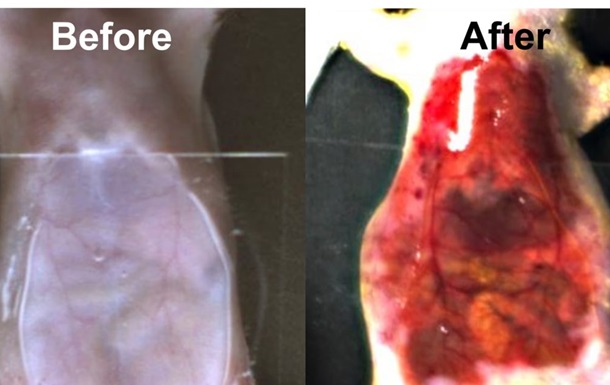

Вчені знайшли спосіб робити шкіру прозорою за допомогою харчового барвника

Використання цього методу допоможе лікарям діагностувати пухлини, не вдаючись до хірургічного втручання.

Дослідники виявили, що звичайний харчовий барвник може тимчасово зробити шкіру, м’язи та інші тканини тварин прозорими, що дозволяє бачити внутрішні органи без інвазивних процедур. Про це повідомляє The Guardian.

Цей метод, поки не випробовували на людях. У ході експерименту барвник був нанесений на шкіру миші, після чого стало можливим побачити її внутрішні органи, такі як печінка, кишківник і сечовий міхур. Після змивання барвника шкіра миші повернулася до звичайного стану.

Науковці вважають, що цей підхід може допомогти діагностувати пухлини та спростити медичні процедури, наприклад, забір крові. Дослідження використало тартразин, звичайний харчовий барвник, який дозволяє світлу проходити через тканини, роблячи їх прозорими. Хоча метод ще не тестувався на людях, він відкриває нові можливості для медицини та наукових досліджень.